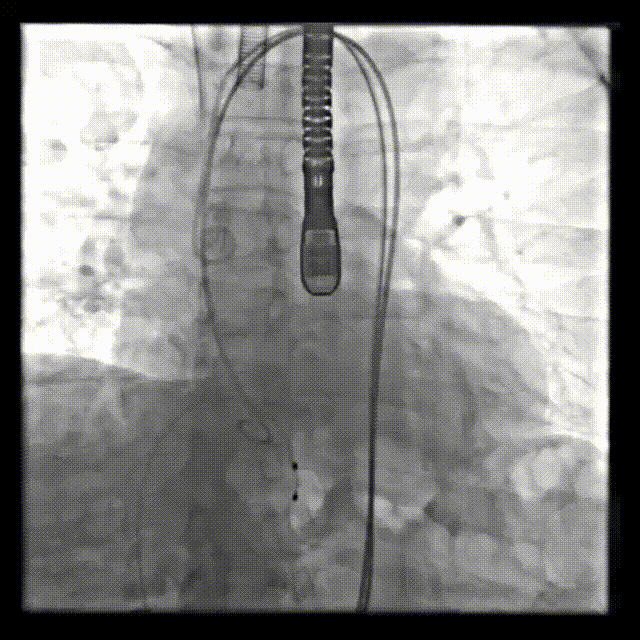

手术效果

成功植入Hanchor Valve(TAV29)瓣膜,术后无反流及瓣周漏。术前左室内压力为111/-5 mmHg,主动脉压力为106/53 mmHg;术后左室内压力为96/2 mmHg,主动脉压力为96/57 mmHg。